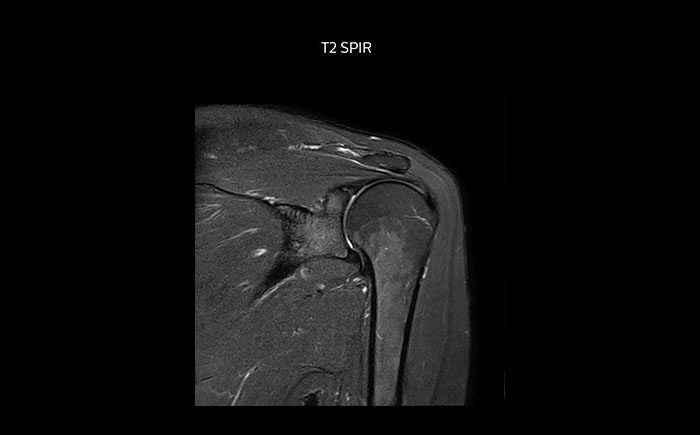

Shoulder MRI with high quality, large coverage

The Prodiva shoulder coil is very flexible and has large coverage, which makes good positioning easier, and that contributes to the superb image quality and high SNR that we get in our shoulder exams.

Scan time 2:55 min, FOV 160 mm,

acq voxels 0.55 x 0.83 x 3.0 mm.

Scan time 4:19 min, FOV 160 mm,

acq voxels 0.55 x 0.80 x 3.0 mm.

Scan time 2:50 min, FOV 160 mm,

acq voxels 0.70 x 0.99 x 3.0 mm.

Shoulder MRI with high quality, T2 SPIR